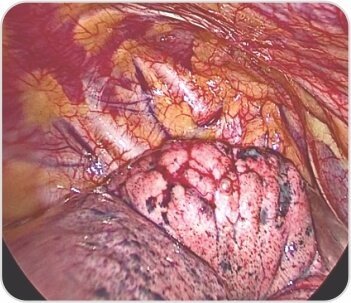

Excised bulla with portion of apical segment